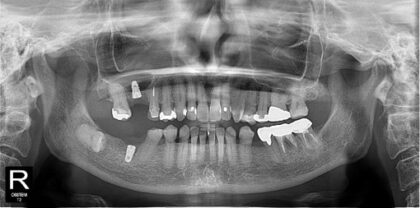

術前レントゲン

術後レントゲン

| 主訴 |

奥歯が痛い。インプラントを含めて治療を相談したい。 |

| 治療内容 |

右下6番、右上6番は歯根破折のため抜歯しインプラント治療を行う事になりました。リッジプリザベーション(抜歯後に骨が吸収するのを防ぐ処置)を行い、抜歯後約2ヶ月でインプラント埋入を行いました。右上6番は上顎洞(副鼻腔)まで3mmの厚みしかなかったため、CGF(骨再生材料)を用いてソケットリフト(副鼻腔の粘膜も持ち上げて骨の高さを作る処置)を行いました。骨結合後に二次手術(インプラントの土台をつける処置)を行い、ジルコニア製上部構造を装着しました。 |